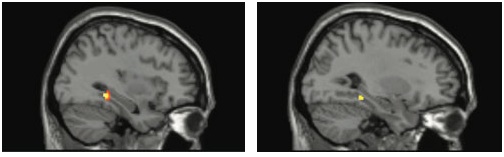

研究人员首先使用了PET(正电子发射断层扫描),随后又使用了fMRI(功能核磁共振成像)证实了PET的扫描结果,两种影像学方法都观察到了相同的结果,增强了观察结果的准确性。研究人员发现两种BDNF基因突变都造成了海马体的异常活动。该基因-激素相互作用影响思维和行为的观察结果与动物实验的结果一致,研究人员怀疑,该影响机制也能增加精神疾病风险。

携带特殊BDNF基因版本的女性,在进行工作记忆处理时,PET扫描图像(左)和fMRI扫描图像(右)都显示了相同的海马体非典型活跃(黄色),这种活跃在正常工作记忆中是一种异常现象。